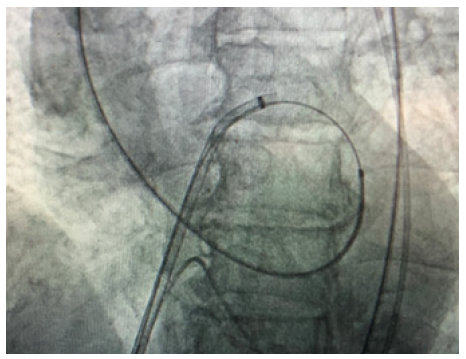

After repeated attempts it was decided to try an alternative approach. The right femoral vein was accessed and an 8F sheath inserted. Transeptal puncture was performed with a Brockenbrough needle and long Terumo wire passed through the left atrium to the left ventricle. The wire could then easily pass retrogradely through the aortic valve down to the descending aorta. The wire was then snared out of femoral artery. A multipurpose catheter was then passed over the wire and antegradely into the left ventricle and the guide wire exchanged. Finally, he nailed the wire to the right sheet of the TAVI. By pulling like this, the wire of the TAVI could cross the calcified valve. The cardiologist after passing the wire through aortic calcified valve put a balloon for the dilatation of the very stenotic valve. This venous-arterial wire loop is used to pass TAVI catheter through aortic valve. After the dilatation of the stenotic aortic valve with the balloon, the procedure continues as standard transfemoral approach. Medtronic Evolut valve was implanted successfully (Figure 1)(Figure 2)(Figure 3).

Figure 2: The wire goes from vena cava, right atrium,left atrium, left ventricle, aorta then femoral artery.